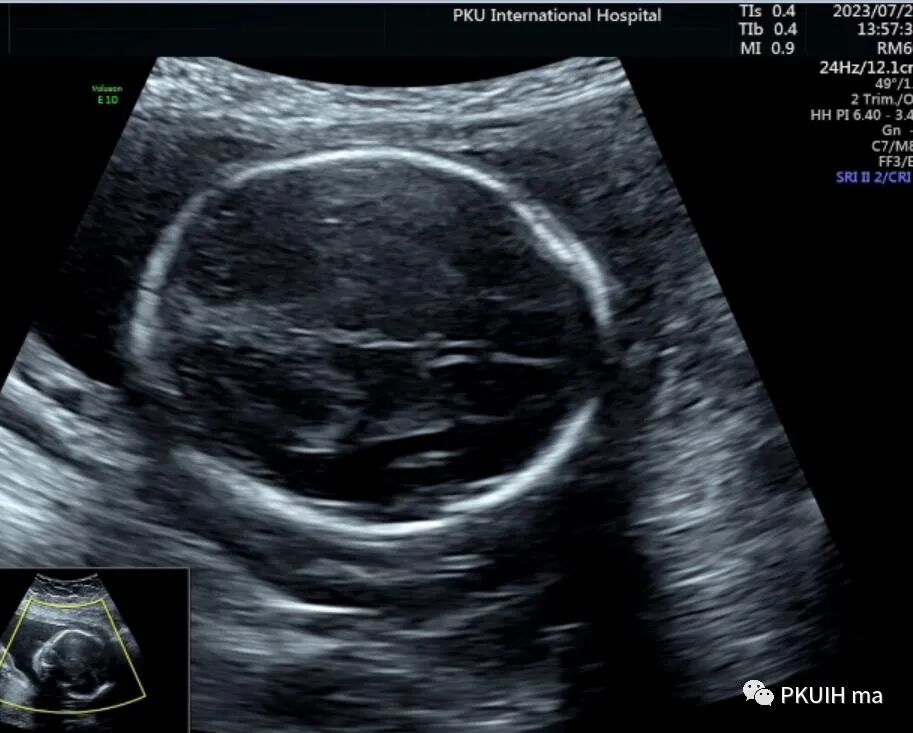

检查中不要把下方的穹窿柱和扩张上抬的三脑室以及融合的侧脑室前角误认为透明隔腔。正常情况下透明隔腔的内径约4-8mm,也有窄的或者宽的,只要形态正常即可,一般大于10mm可以报增宽,小于2mm考虑窄。此时需要关注透明隔腔的形态,一般透明隔腔呈长方形,个别的可以呈三角形,如果左右径大于前后径时认为形态异常。超声显示呈正方形或反长方形、圆形或者是前后径/左右径<1.5时要仔细观察胼胝体,以除外胼胝体发育异常。

妊娠18周前或37周后透明隔腔可以不显示,如果在18-37周之间未发现透明隔腔,要重点观察胼胝体、侧脑室、脑中线、视神经等,最好做个胎儿神经系统筛查,以排除前脑无裂畸形、胼胝体缺失、视-隔发育不良和孤立性透明隔发育不良、脑积水、孔洞脑、脑裂畸形、积水性无脑畸形、脑膨出等。透明隔腔缺失是完全性胼胝体缺失的重要标志,透明隔腔缺失合并“泪滴状”的侧脑室是提示胼胝体缺失的重要线索(如下图),此时一定要重点扫查胼胝体,包括二维及血流等,正中矢状切面是必不可少的扫查。